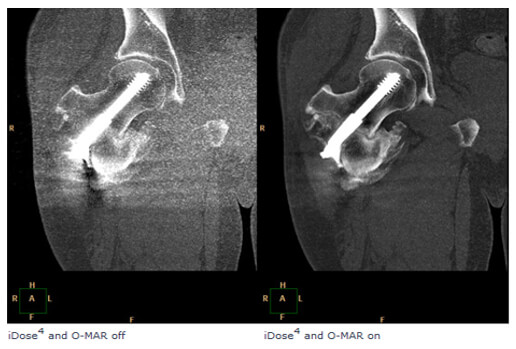

Metal implants such as shrapnel, surgical clips, pacers, joint prostheses, wires, pedicle screw placement, stenting, usually undergo follow-up CT imaging. These metallic implants lead to severe streak and shadow artifacts in CT images that superimpose the structures of interest and deteriorate image quality. This is because metallic objects are a high-density material, which is strongly scattered to the transmitted x-ray beam during CT examination.

Various metal artifact reduction techniques have been developed to reduce metal artifacts, and the most commonly used reconstruction algorithm for CT has filtered back projection (FBP), interpolation methods, and iterative reconstruction methods.

Streaking caused by over ranging can be greatly reduced using special software corrections. Manufacturers use a variety of interpolation techniques designed to substitute the over ranged values in attenuations’ profile.

However, there is always a detail loss around the metal/tissue interface, which is often the area of interest in diagnosis.

This image shows the effectiveness of metal reduction artifact software. Notice how much better the resolution is in the image on the right.